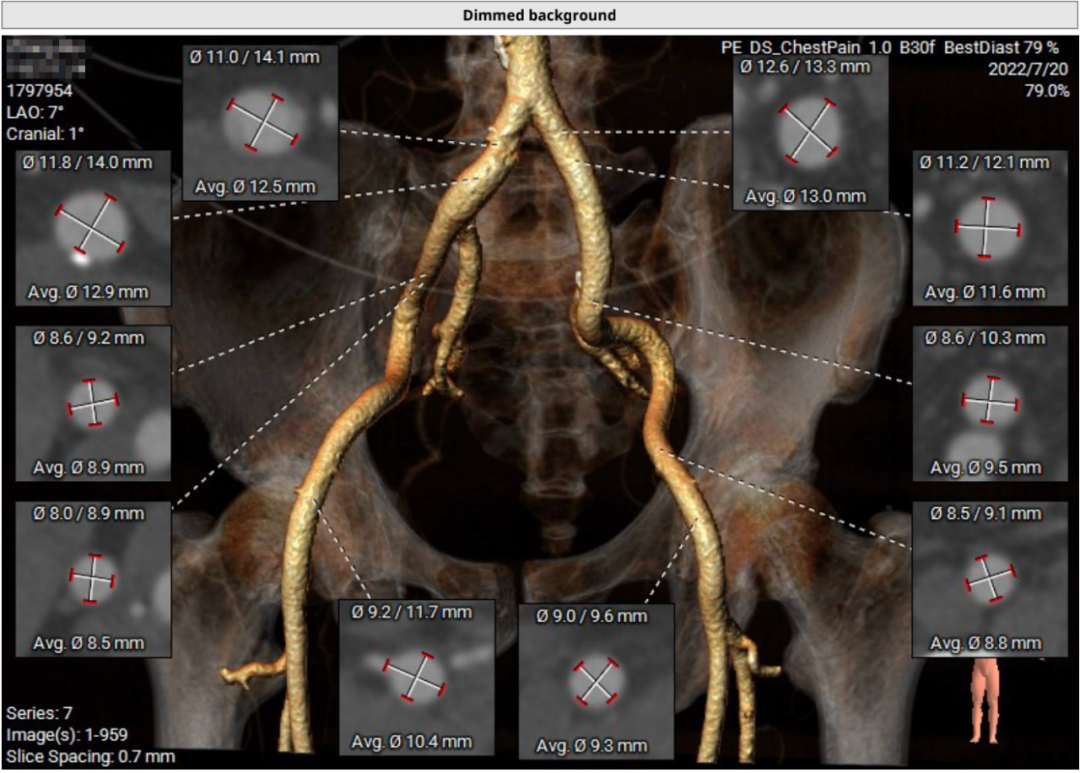

患者64岁男性,Type 0 型二叶瓣、横位心。主动脉瓣中度狭窄,重度反流,瓣环周长92.0mm,平均径29.0mm。LVOT周长98.7mm,升主扩张,窦部结构极限,锚定能力极限。入路两侧血管轻度迂曲,分叉高度可,两侧血管内径均>8mm。

首先,最重要的是观察瓣环结构,理论上如果瓣环周长超过85mm,尽量就不做;第二,看流出道情况,最好是直筒状的,瓣环和瓣下4mm的直径比值,理论上不能超过1:1.1,如果超过1.1以上就变成喇叭状,也不建议做;第三,避免存在升主动脉显著扩张,如果扩张明显,无法提供有效的锚定。总体来说,最主要的一定是瓣环直径,瓣叶有没有增厚,瓣叶有没有钙化,瓣环能否有效固定住植入的瓣膜。瓣环的固定和锚定条件,是反流患者能否进行TAVR的决定因素。